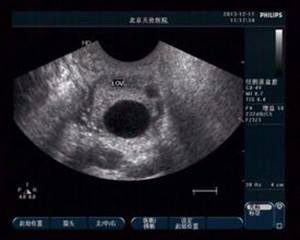

未破裂卵泡黃素化綜合征(LUFS) 是指卵泡成熟達到18mm以上直徑,LH或hCG峰值出現,但卵泡不“破裂”,卵子不能排出,而在卵泡里黃素化萎縮了。LUFS患者的卵泡能分泌相應的雌、孕激素,基礎體溫呈雙相,子宮內膜呈分泌期改變,具有規律的月經周期,所以在臨床表現上難與正常排卵區分。

(圖:超聲示未破裂的卵泡)

1、陰道超聲:我們對LUFS的診斷,一般是根據自然周期LH峰值,或HCG注射48h后卵泡仍然沒有塌陷或消失的超聲影像來做出的。由于有時排卵后卵泡壁塌陷的超聲征象并不典型,或排卵后的卵泡有時也并不塌陷,在外觀上也難以判斷,因此僅憑超聲圖像診斷可能有一定的局限性。